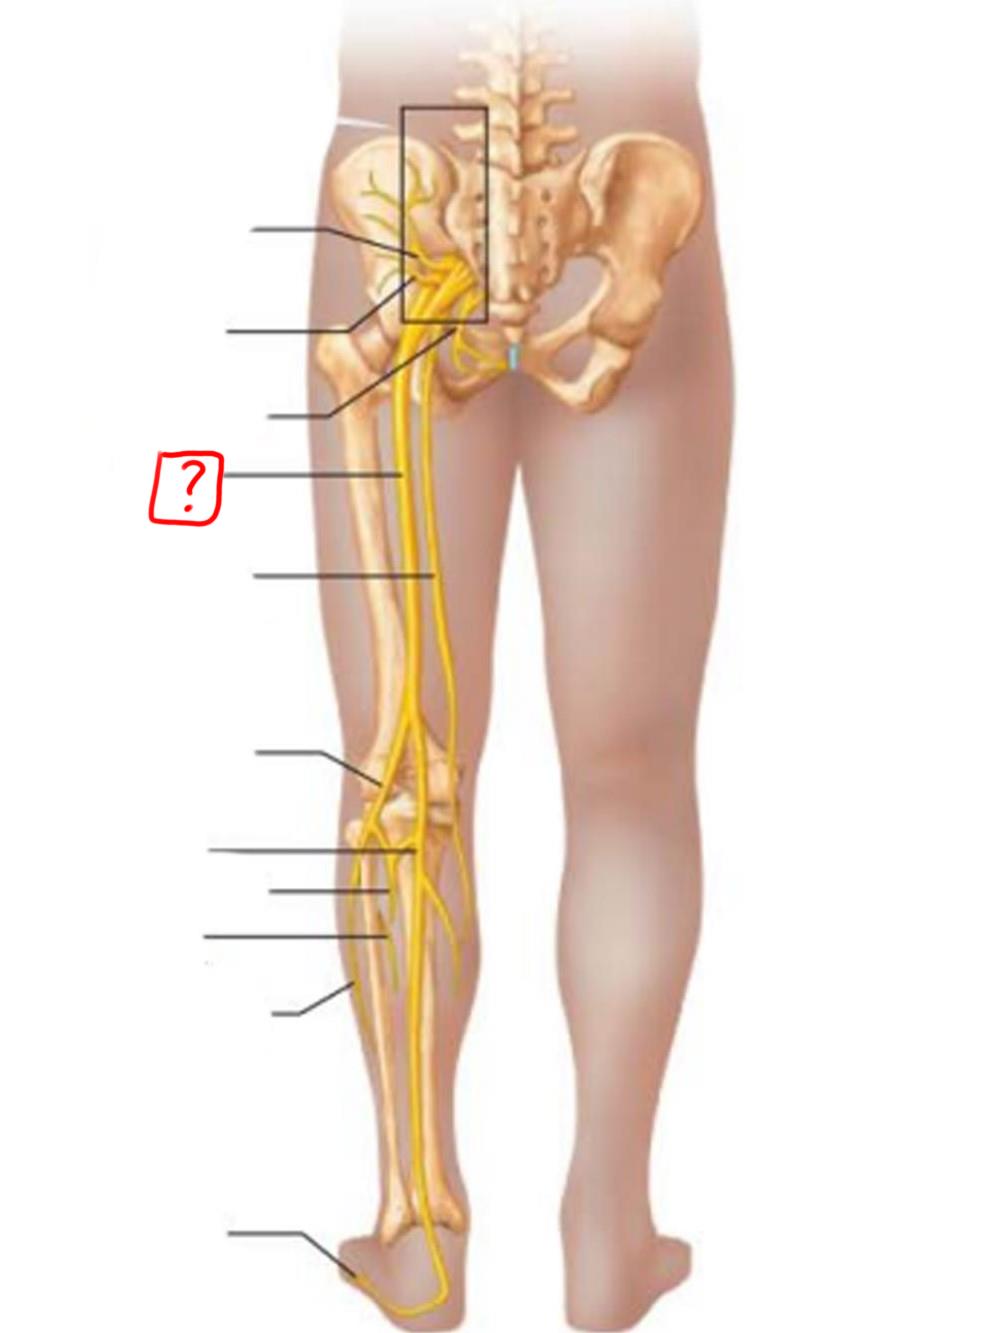

obturator

femoral

lumbosacral trunk

iliohypogastric

ilioinguinal

femoral

lateral femoral cutaneous

obturator

anterior femoral cutaneous

saphenous

superior gluteal

inferior gluteal

pudendal

sciatic

posterior femoral cutaneous

common fibular

tibial nerve

sural (cut)

deep fibular

superficial fibular

plantar branches

superior gluteal

lumbosacral trunk

inferior gluteal

common fibular

tibial

posterior femoral cutaneous